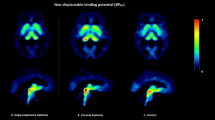

Frank GK, Bailer UF, Henry SE, Drevets W, Meltzer CC, Price JC et al (in press). Increased Dopamine D2/D3 receptor binding after recovery from Anorexia Nervosa measured by positron emission tomography and [11C]raclopride. Biol Psychiatry.